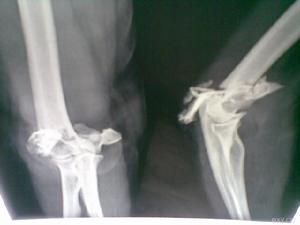

肱骨外髁骨折x片X線照片顯示肱骨小頭的骨折線多超過化骨核的1/2,或不通過小頭化骨核,而通過肱骨小頭與滑車間溝的軟骨在乾骺端處有一骨折線。骨折塊可向外側移位。骨折脫位型X線片,正位片顯示骨折塊連同尺橈骨可向橈側或尺側移位,側位片顯示可向後側移位,偶可見向前移位者。肱骨外髁骨折在X線片上表現為多種多樣,在同一骨折類型中表現也常不一。